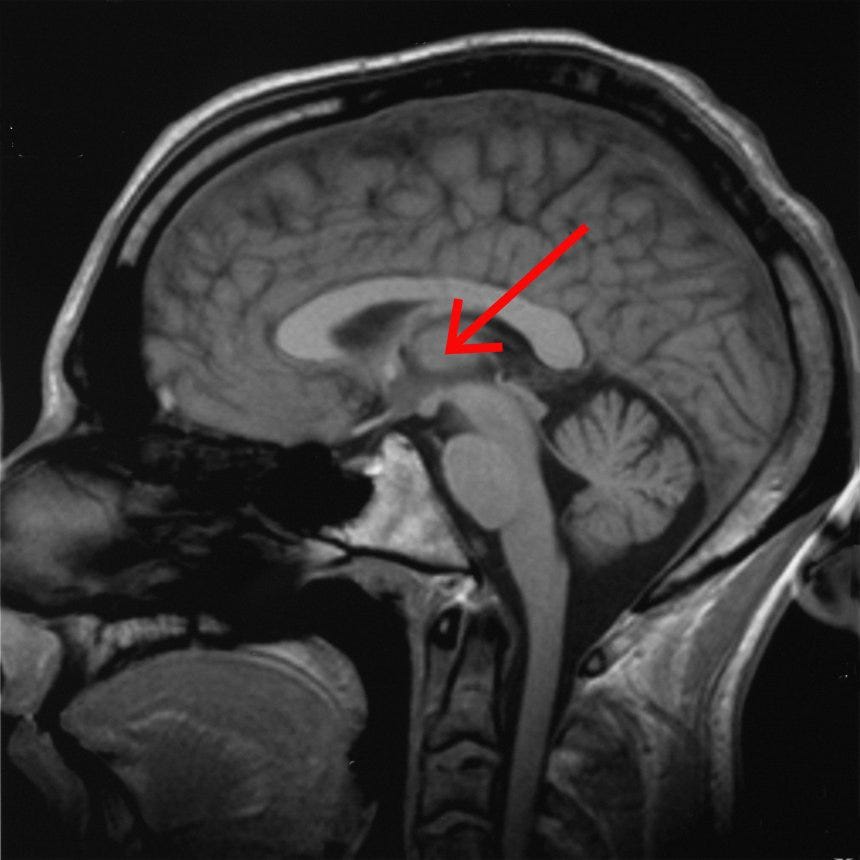

the red arrow points to the thalamus In the past 3 entries in my consciousness sequence I was focused on conscious sensory perception — the differen…